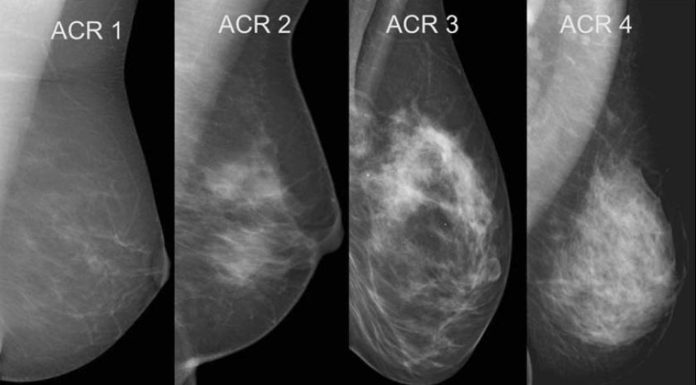

Exame de tomossíntese se mostra o mais eficiente para diagnosticar câncer de mama